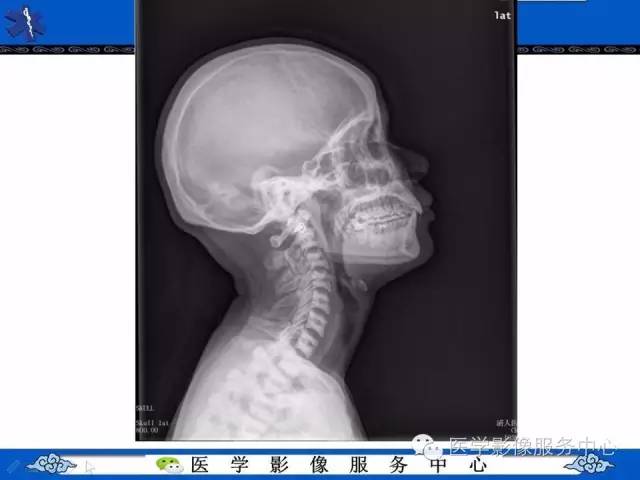

【PPT】石骨症——少见的骨病例,但是过目不忘!